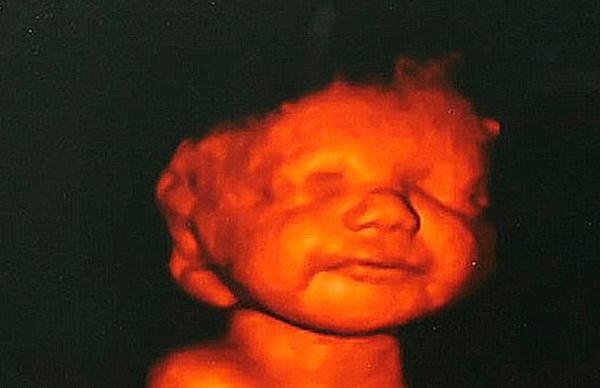

Información General | Katyia Rowe, una inglesa de 26 años, decidió no hacerse un aborto pese a que, según los médicos, el cerebro del bebé no se había formado bien y podría tener graves consecuencias. Finalmente la criatura murió a las nueve horas.